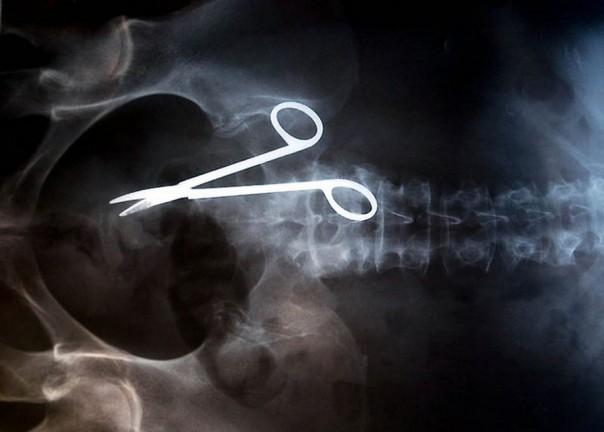

Сувенир от хирурга. После успешной операции по удалению раковой опухоли пациент продолжил жаловаться на сильные боли. Сперва ему сказали, что так и должно быть после хирургического вмешательства. Но спустя месяц врачи обнаружили источник боли: в теле пациента был забыт 13-сантиметровый инструмент. Подобная ошибка обошлась клинике в 97 тысяч долларов США, которые пациент успешно отсудил у медицинского учреждения.